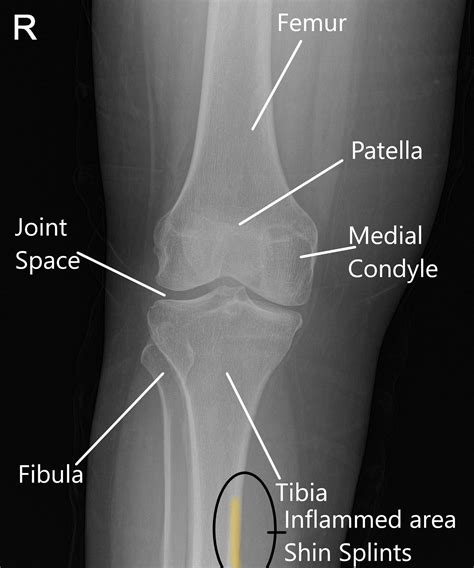

Shin Splints(Shin pain)? Sports massage can help!

Shin Splints(Shin pain)? Sports massage can help!